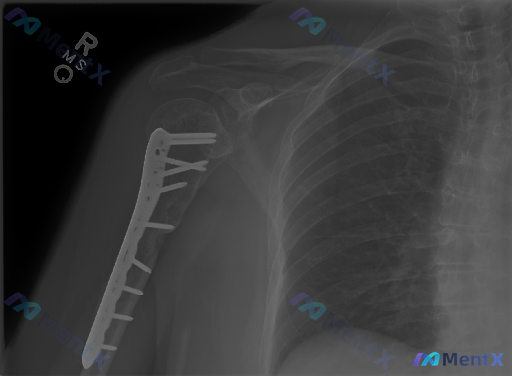

这张右肱骨近端骨折术后X光,最需要警惕的异常是什么?

整理了一份右肱骨近端骨折内固定术后的影像资料,想和大家讨论一下读片思路。

- 肱骨近端有金属内固定钢板螺钉系统,位置贴附外侧皮质

- 大结节及外科颈区域可见骨折断端,透亮线存在,部分区域骨痂形成不明显

- 肱骨头与肩胛盂对位基本尚可,肩锁关节、锁骨、肩胛盂未见明显异常

- 周围软组织因金属伪影干扰,滑囊肌腱区域显示不清